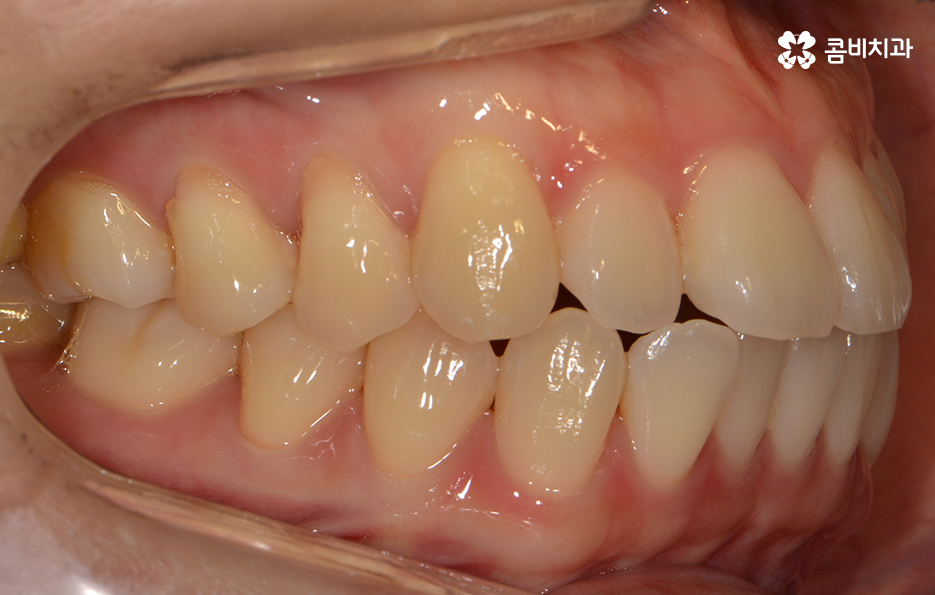

돌출된 앞니로 인해서 교정을 원하신 상황이며 치료 전 치아 상태

치열의 상태가 정면으로 바라봤을 때 비교적 가지런한 편이지만

측면으로 볼 때 유독 앞으로 돌출된 경우라면

입모양과 얼굴형에도 영향을 주기 때문에

치료가 시작되기 전 치아 상태

돌출치아로 인한 돌출입이나 앞니의 벌어짐이 비교적 심하지

않은 분들이라고 하더라도 모델이나 서비스직 등에서

종사하거나 외모에 대한 관심이 많으신 분들의 경우에는

보다 나은 심미적인 만족감을 얻길 원하시는 경우가 많습니다.